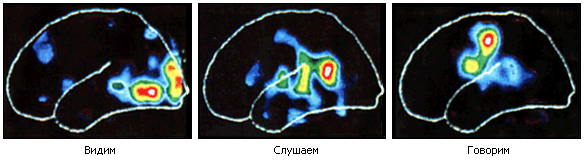

Рис. 73. Прибор фиксирует, какие области коры головного мозга участвуют в актах зрения, слуха и речи. Чем ярче цвет, тем активнее нейроны